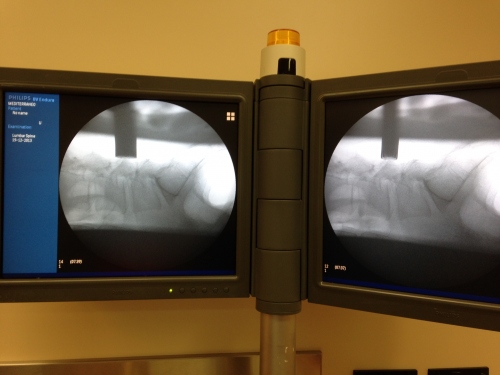

Ο σωληνωτός αυτός διαστολέας εισέρχεται με τη βοήθεια οδηγού βελόνης υπό ακτινοσκοπικό έλεγχο( C arm) και σταθεροποιείται με ειδικό βραχίονα.